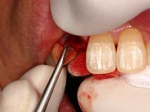

前歯即時埋入症例

術前術前主訴-前歯が腫れて痛い。治療法のうち、ブリッジとインプラントを説明して隣の前歯を削らないですむことからインプラントを選択された。 術前レントゲン術前レントゲン術前レントゲン 抜歯抜歯抜歯を行う。折れていた位置がかなり深い位置であるのがわかる。 歯根も抜歯歯根も抜歯

歯根も抜歯歯根も抜歯歯根も抜歯 抜歯した穴をよく掃除抜歯した穴をよく掃除抜歯した穴をよく掃除(掻爬)後すぐにインプラントを埋入 埋入直後のレントゲン埋入直後のレントゲン埋入直後のレントゲン。上部に見えるのは抜いた歯を利用して両どなりの歯に接着して一時的に使えるようにした。 二次オペ時二次オペ時

仮の支柱を装着仮の支柱を装着仮の支柱を装着 作業模型上のセラミック上部構造作業模型上のセラミック上部構造作業模型上のセラミック上部構造 術後術後術後